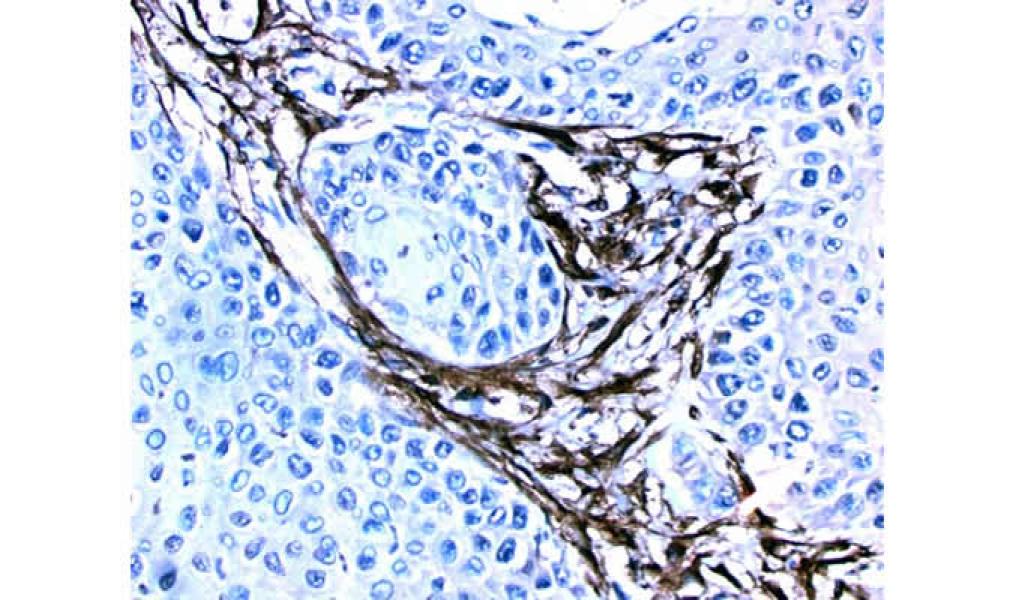

Human pancreatic cancer pathological sample showing a pro-tumor desmoplastic phenotype. Image adapted from Alexander & Cukierman Matrix Biology 2020 and depicts central discoveries included in Franco-Barraza et al eLife 2017. Image credit Neelima Shah and Edna Cukierman